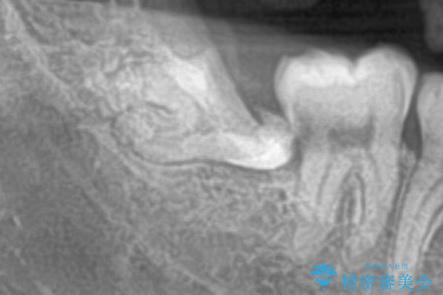

- 親知らずが痛くて抜いて欲しいとの事で来院。CTで神経の位置を確認し、抜歯を行いました。

抜歯後、奥歯にも虫歯があったので虫歯を拡大鏡下で取りきり、メタルインレーにて治療を行いました。